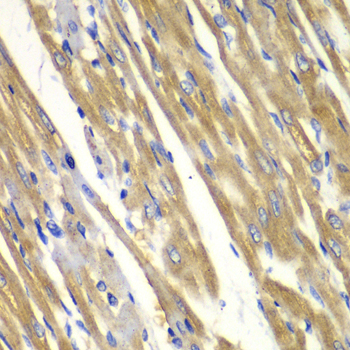

Immunohistochemistry of paraffin-embedded rat heart using TYR antibody at dilution of 1:100 (40x lens).

IHC 1:50 - 1:200